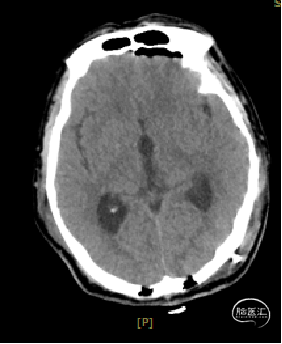

术后1天复查CT

术区无出血,脑室系统较术前显著缩小,脑积水缓解。